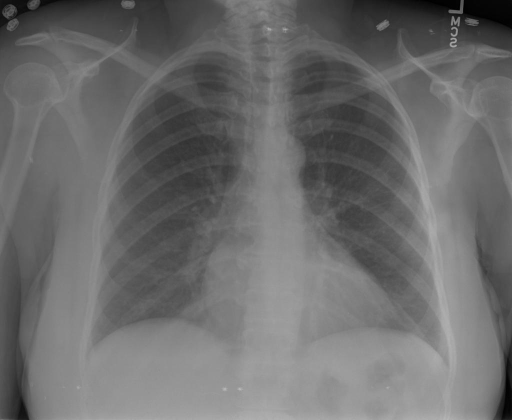

# 本文贡献  - 借助ChatGPT以及公开的数据集,我们构造了一个`X光影像-诊断报告`对的医学多模态数据集; - 我们将构建的中文胸部X光片诊断数据集在[VisualGLM-6B](https://github.com/THUDM/VisualGLM-6B)进行微调训练,并开放了部分训练权重用于学术研究; # 数据集 - [MIMIC-CXR](https://physionet.org/content/mimic-cxr-jpg/2.0.0/)是一个公开可用的胸部X光片数据集,包括377,110张图像和227,827个相关报告。 - [OpenI](https://openi.nlm.nih.gov/faq#collection)是一个来自印第安纳大学医院的胸部X光片数据集,包括6,459张图像和3,955个报告。 在上述工作中,报告信息都为非结构化的,不利于科学研究。为了生成合理的医学报告,我们对两个数据集进行了预处理,并最终得到了可以用于训练的**英文报告**。除此之外,为了更好的支持中文社区发展,借助ChatGPT的能力,我们将英文报告进行了中文翻译,并最终形成了可用于训练的数据集。 |数据集|数量|下载链接| |:-|:-|:-| |MIMIC-CXR-zh|-|-| |OpenI-zh|6,423|[诊疗报告](./data/Xray/openi-zh.json) 、[X光影像](https://pan.baidu.com/s/13GBsDMKf6xBZBSHpoWH_EA?pwd=k9sh)| # 快速上手 1. 安装环境 ```bash # 安装依赖 pip install -r requirements.txt # 国内换源安装依赖 pip install -i https://mirrors.aliyun.com/pypi/simple/ -r requirements.txt ``` 此时默认会安装`deepspeed`库(支持`sat`库训练),此库对于模型推理并非必要,同时部分`Windows`环境安装此库时会遇到问题。 如果想绕过`deepspeed`安装,我们可以将命令改为: ```bash # 安装依赖 pip install -i https://mirrors.aliyun.com/pypi/simple/ -r requirements_wo_ds.txt # 安装SwissArmyTransformer pip install -i https://mirrors.aliyun.com/pypi/simple/ --no-deps "SwissArmyTransformer>=0.3.6" ``` 2. 模型推理 CLI推理: ```python python cli_demo.py --from_pretrained checkpoints/finetune-XrayGLM-05-25-01-04 --prompt_zh '详细描述这张胸部X光片的诊断结果' ``` 更多[参数](https://github.com/WangRongsheng/XrayGLM/blob/main/cli_demo.py#L16) # 效果展示 诊断: |X光影像|诊疗报告(医生)|XrayGLM| |:-|:-|:-| ||根据X射线图像,心脏大小正常,肺部看起来很清晰。已经排除了肺炎、积液、水肿、气胸、腺病、结节或肿块的存在。该发现表明一切正常。换句话说,总体印象是胸部正常。|X光片显示,心脏大小正常。肺部没有气胸或胸腔积液的证据。骨骼结构看起来没有任何异常。总的来说,X光片表明没有发现急性心肺疾病的迹象。| ||X光图片显示没有扭曲的区域、可疑的骨质不透明度或胸腺积液。心脏大小轻微增大,但非常稳定。此外,没有气胸的证据,肺野也正常。总体来说,X光片显示没有急性心脏异常,但要注意轻微的心脏扩大。|X光片显示,心脏大小正常。肺部和纵隔轮廓清晰,没有气胸或胸腔积液的证据。骨骼结构完整,没有任何急性异常。| ||心影形态在正常范围内。没有急性骨质异常。有可能出现没有明显的吸水或肺实质状况的线索。没有大面积积液或气胸。有可能怀疑其有误吸或肺实质问题。为了确诊和治疗,可能需要进行适当的影像学随访。|心脏大小正常,肺部和纵隔轮廓清晰。没有急性异常或活动受限的证据。没有任何明显的气胸、胸腔积液或肺不张的迹象。此外,也没有发现任何局灶性骨质异常或其他急性疾病。| 多轮对话: |X光影像|诊疗报告(医生)| |:-|:-| ||右侧主动脉突出观察到。心脏大小正常。胸部未发现明显的肺气肿、胸膜积液或可疑的肺部病变。报告指出已知右侧主动脉情况正常。| ```bash >> X光影像路径:./data/Xray/861_1.png >> 用户:这是一张什么图? >> XrayGLM:这张图片显示的是一张肺部检查的X光片。 >> 用户:请描述这张胸部X光片的诊断结果 >> XrayGLM:心脏大小正常,肺部清晰。没有急性心肺疾病的证据。 >> 用户:是否存在肺气肿? >> XrayGLM:没有肺气肿。心脏大小正常,肺部清晰。没有发现急性心肺疾病的证据。 >> 用户:平时饮食该注意什么? >> XrayGLM:饮食应该健康,均衡。建议增加蛋白质的摄入量,因为蛋白质有助于维持肌肉和骨骼的健康。多食用蔬菜、水果、全谷物以及健康的脂肪来源如橄榄油、鱼类等可以帮助获得足够的维生素和矿物质。此外,避免过度饮酒或吸烟,这些习惯可能会对心脏健康产生负面影响。 ``` # 项目致谢 1. [VisualGLM-6B](https://github.com/THUDM/VisualGLM-6B)为我们提供了基础的代码参考和实现; 2. [MiniGPT-4](https://github.com/Vision-CAIR/MiniGPT-4)为我们这个项目提供了研发思路; 3. ChatGPT生成了高质量的中文版X光检查报告以支持XrayGLM训练; 4. [gpt_academic](https://github.com/binary-husky/gpt_academic)为文档翻译提供了多线程加速; 5. [MedCLIP](https://github.com/RyanWangZf/MedCLIP) 、[BLIP2](https://huggingface.co/docs/transformers/main/model_doc/blip-2) 、[XrayGPT](https://github.com/mbzuai-oryx/XrayGPT) 等工作也有重大的参考意义;  这项工作由[澳门理工大学应用科学学院](https://www.mpu.edu.mo/esca/zh/index.php)硕士生[王荣胜](https://github.com/WangRongsheng) 、[段耀菲](https://github.com/IsBaSO4) 、[李俊蓉](https://github.com/lijunrong0815)完成,指导老师为檀韬副教授、[彭祥佑](http://www.patrickpang.net/)老师。 *特别鸣谢:[USTC-PhD Yongle Luo](https://github.com/kaixindelele) 提供了有3000美金的OpenAI账号,帮助我们完成大量的X光报告翻译工作 # 免责声明 本项目相关资源仅供学术研究之用,严禁用于商业用途。使用涉及第三方代码的部分时,请严格遵循相应的开源协议。模型生成的内容受模型计算、随机性和量化精度损失等因素影响,本项目无法对其准确性作出保证。即使本项目模型输出符合医学事实,也不能被用作实际医学诊断的依据。对于模型输出的任何内容,本项目不承担任何法律责任,亦不对因使用相关资源和输出结果而可能产生的任何损失承担责任。 # 项目引用 如果你使用了本项目的模型,数据或者代码,请声明引用: ```bash @misc{wang2023XrayGLM, title={XrayGLM: The first Chinese Medical Multimodal Model that Chest Radiographs Summarization}, author={Rongsheng Wang, Yaofei Duan, Junrong Li, Patrick Pang and Tao Tan}, year={2023}, publisher = {GitHub}, journal = {GitHub repository}, howpublished = {\url{https://github.com/WangRongsheng/XrayGLM}}, } ``` # 使用许可 此存储库遵循[CC BY-NC-SA](https://creativecommons.org/licenses/by-nc-sa/4.0/) ,请参阅许可条款。